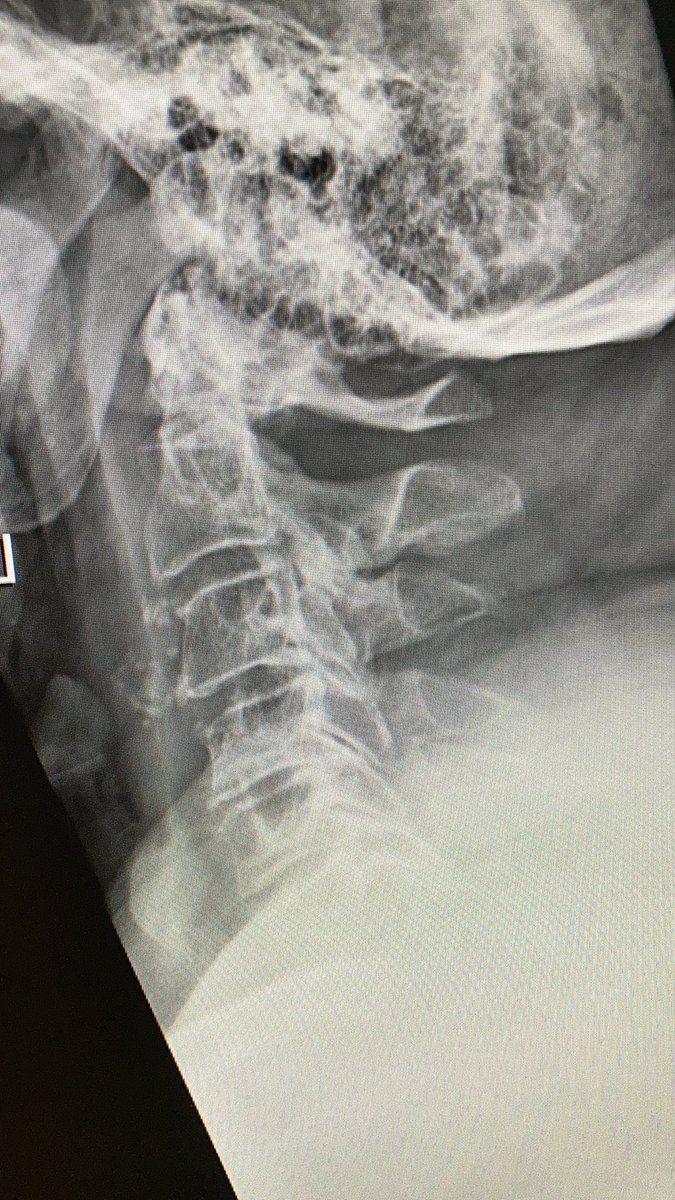

this is a #odontoid process/dens axis in a patient with radiculomyelopathy.

osteoarthritis of the atlantodental joint is present, too

4 years later (after ACDF), he fell and sustained odontoid fracture type II according to Anderson/d’Alonzo. you see the fracture line - and no, it’s not “incomplete”, it’s for sure complete, just the positioning in the CTscan. As pain was no problem, we’ve put him in a collar

what would you have recommended in this 68yo patient if he was in your hospital?